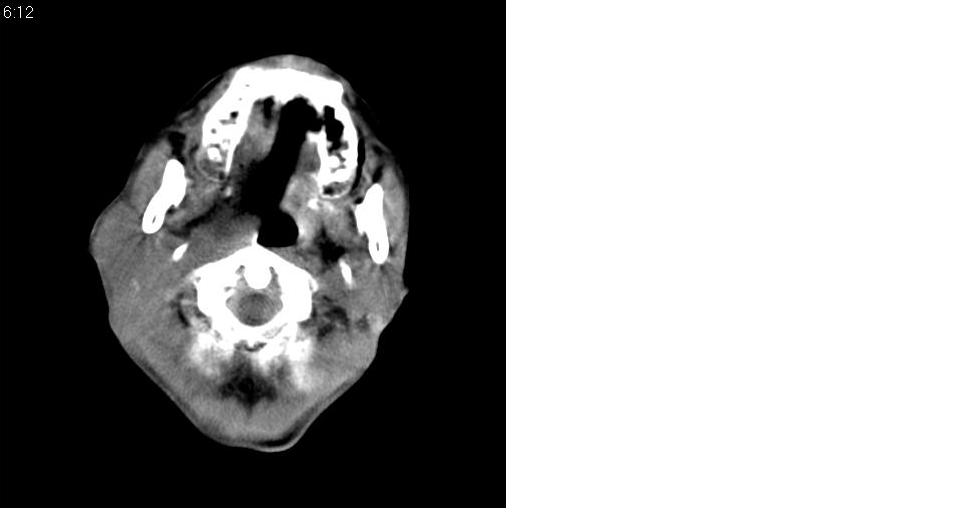

男 70岁,右侧颈部包块八个月余,下午及夜间疼痛加剧,包块质硬。化验穿刺镜下可见大量成堆裸核上皮细胞,可符合结核性淋巴结炎。

右侧颈部不规则软组织密度肿块影,密度均,边缘不清,颈筋膜间隙闭塞,向内致口喉咽受压变形,外达胸锁乳突肌深部,与之分界不清,周围骨质未见异常。

喉癌伴颈部淋巴结转移,不除外喉结核,颈部淋巴结结核。

考虑喉癌伴右侧颈部淋巴结转移,结核待排。